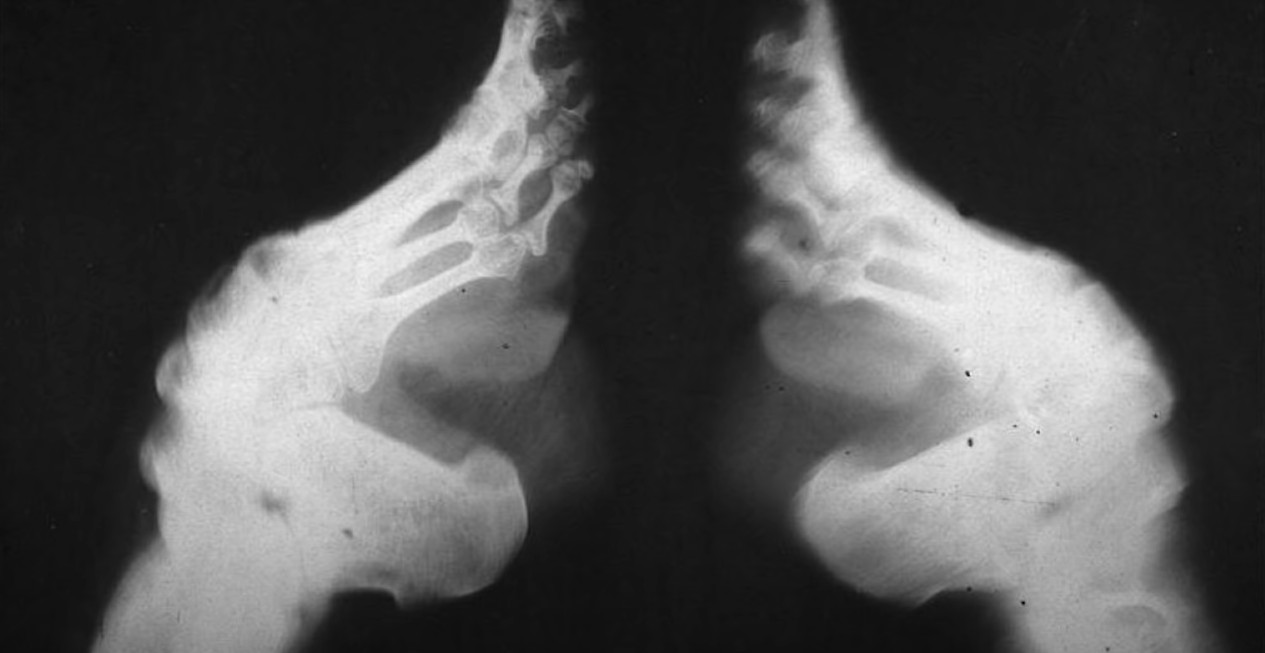

Везивање стопала, ради њиховог смањења је културна пракса, која је постојала у Кини од 10. века до успостављања Народне Републике Кине 1949. године, која је укључивала чврсто превијање стопала жена како би се променио њихов облик у естетске сврхе.

Везивање стопала обично би почињало када су девојчице имале између 4 и 6 година; неке су имале само 3 године, а неке чак 12 година. Мајке, баке или старије женске родбине прво су везивале девојчицама стопала. Крајњи циљ је био да стопала буду дугачка 7,5 цм, идеално стопало „златног лотоса“, иако је мало појединаца заиста постигло тај циљ. Четири мања прста су била увучена испод, повучена према пети и умотана завојима.

Сваки пут када су стопала одвезана, завоји и стопала су очишћени. Сва мртва кожа, пликови, осушена крв и гној су уклоњени. Процес је могао изазвати парализу, гангрену, улцерацију или смрт, иако је смрт била ретка. Везивање стопала наставило се до краја живота девојчице. Преко завоја су се носиле украсне ципеле и хеланке које су се могле разликовати у зависности од доба дана и прилике.